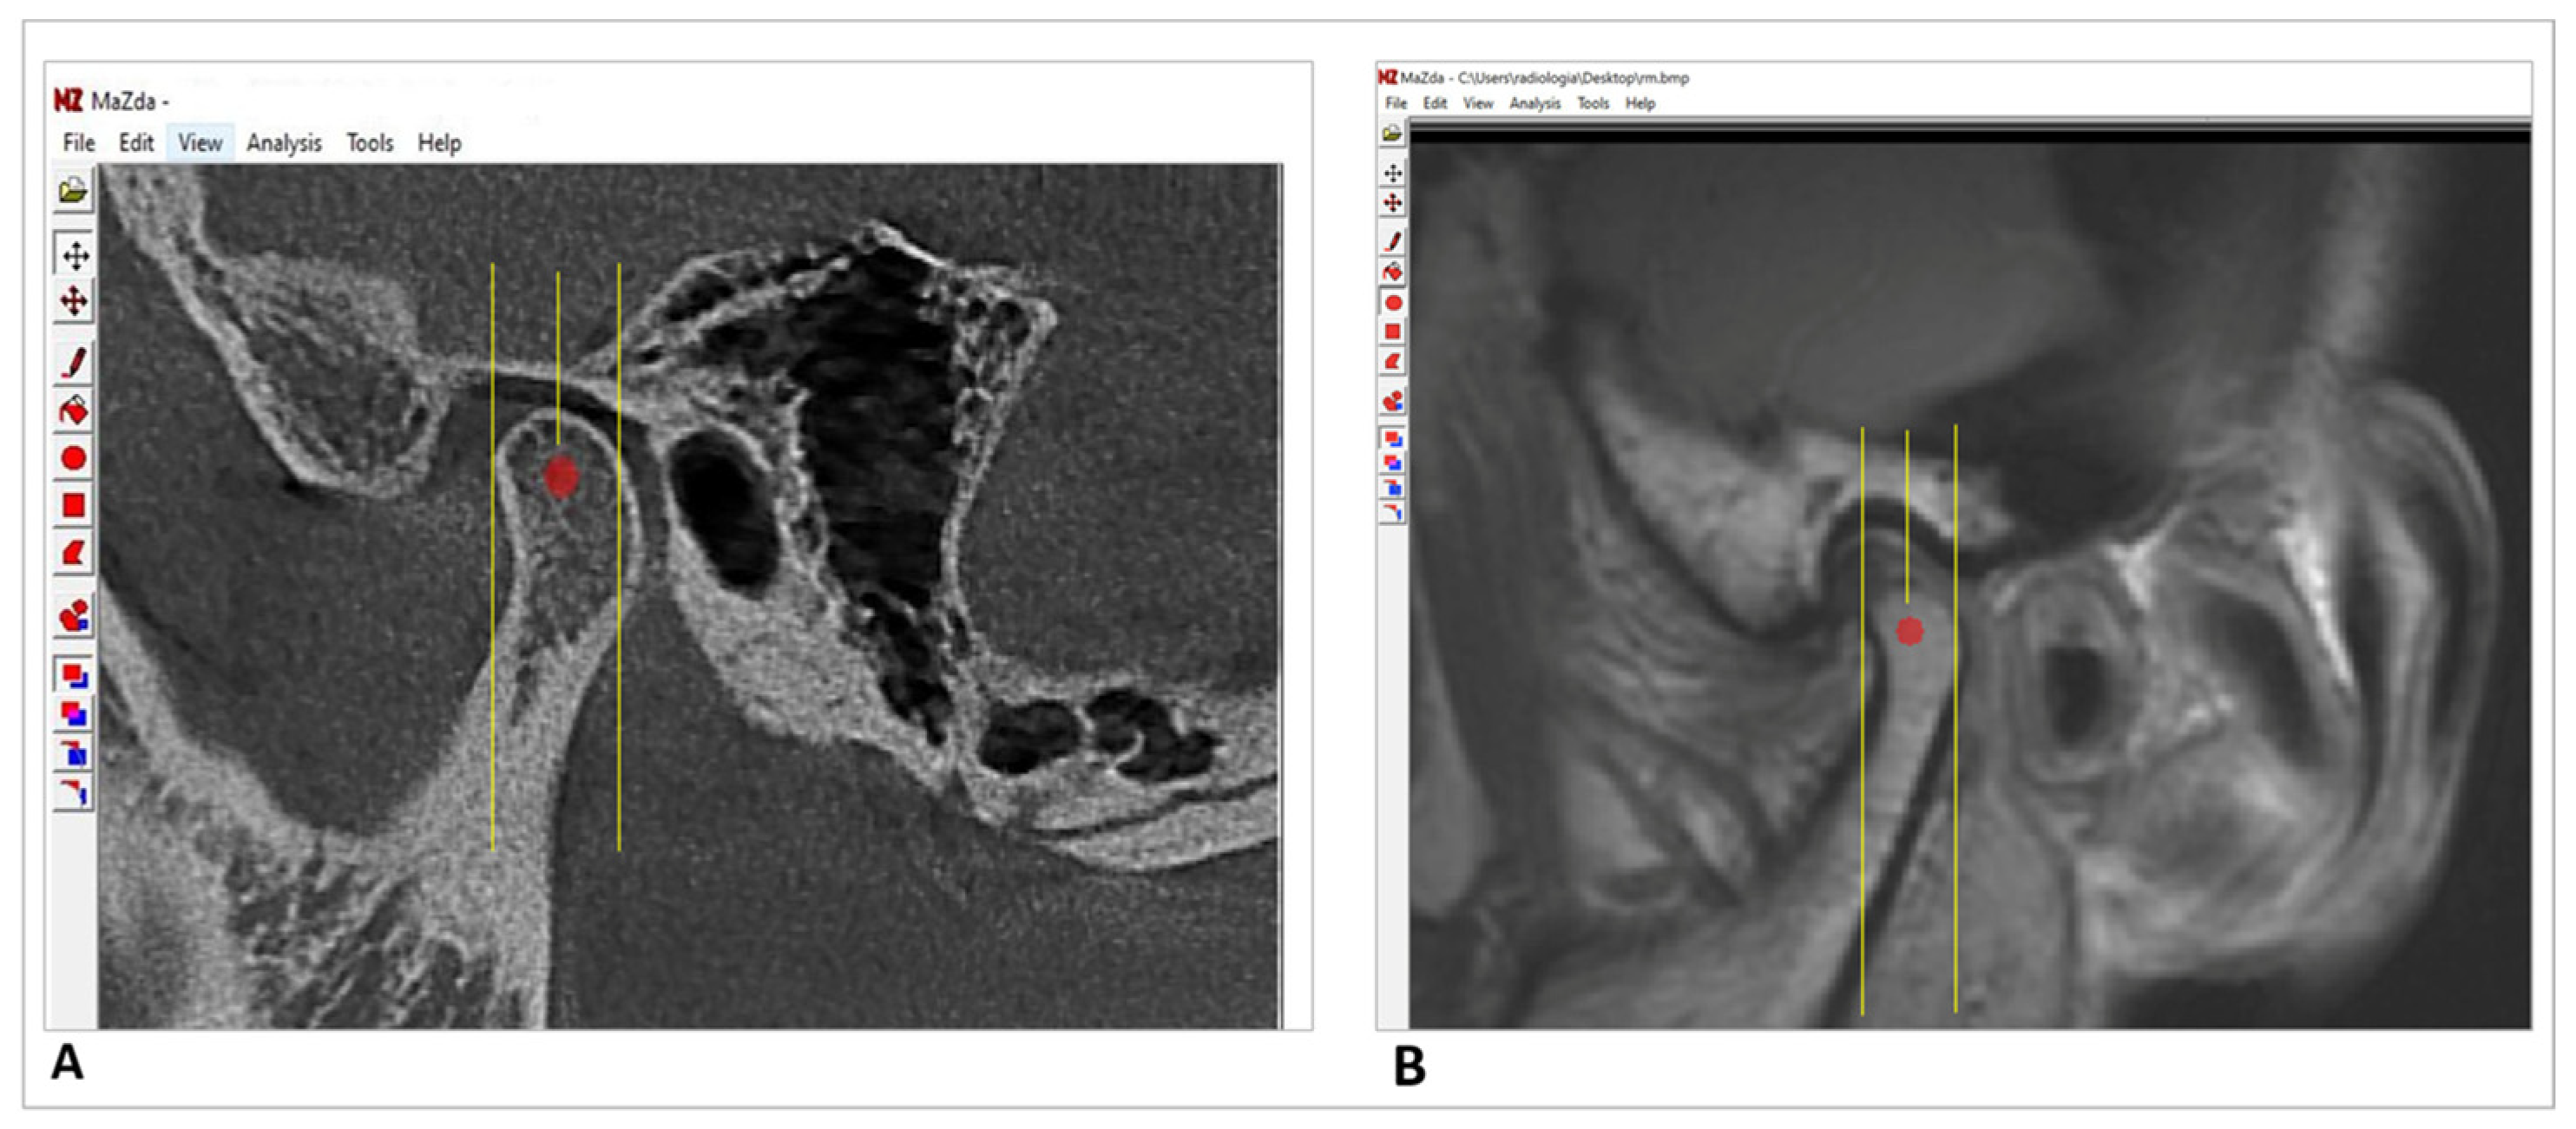

2.2. Image Analysis

2.3. Extraction and Analysis of Texture Features